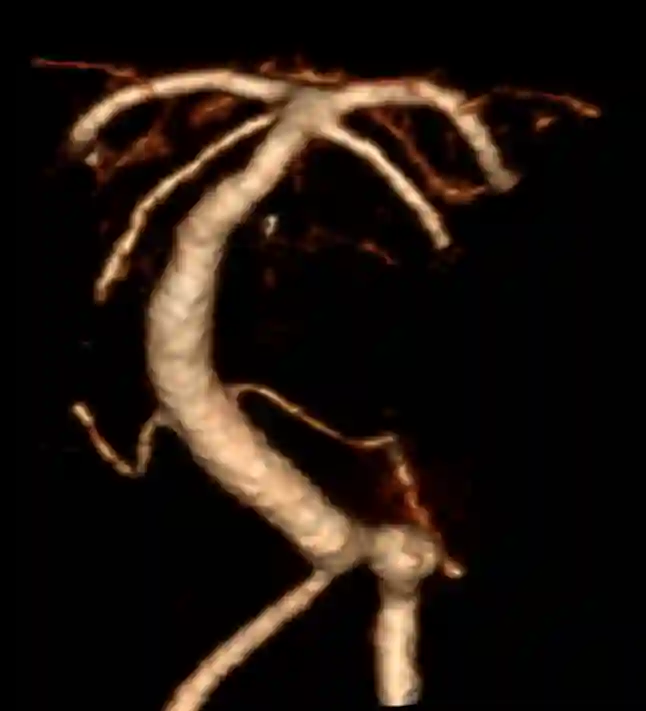

Bildgebung

Der Goldstandard zur optimalen Darstellung der Arteria vertebralis ist die digitale Subtraktionsangiographie, kann jedoch je nach klinischer Fragestellung auch in der CT-Angiographie oder MRT Bildgebung dargestellt wird.

Aneurysmen

Im Bereich der Arteria vertebralis können typischerweise Dissektionsaneurysmen auftreten und eine Subarachnoidalblutung verursachen[^3]. Die Behandlung dieser Dissektionsaneurysmen kann je nach Fall beispielsweise endovaskuläre mithilfe von Implantation eines Flow-Diverters behandelt werden[^4] [^5].